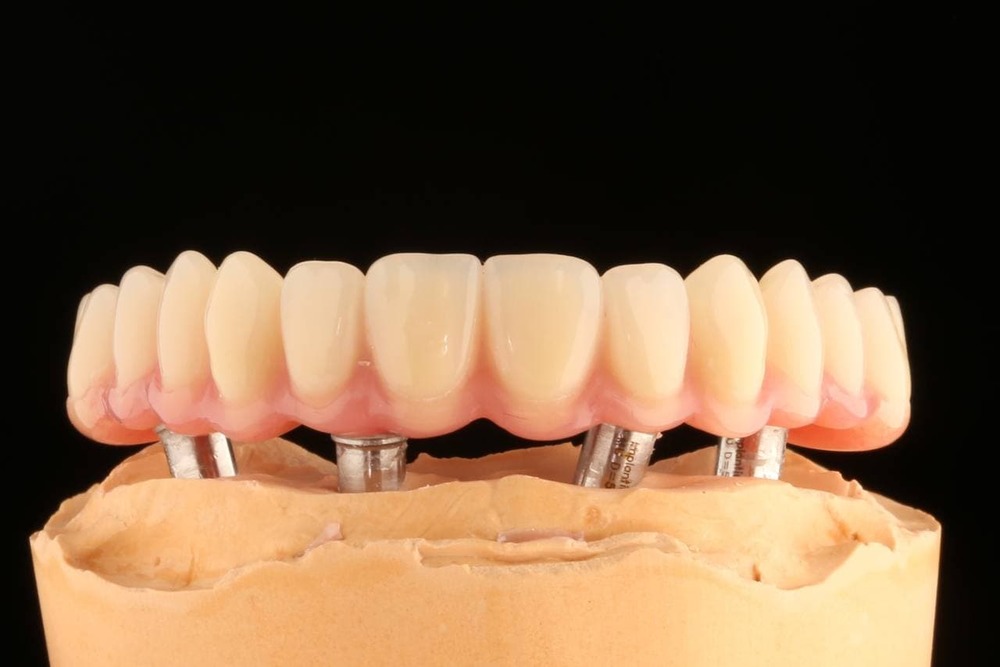

А так на модели

При технологии «всё на 4» устанавливается четыре основных импланта: два в проекции вторых зубов, и ещё два — под углом, чтобы шахта импланта вышла под пятым и шестым зубом. И эти четыре атланта держат весь челюстной протез. Выглядит это так:

Протезирование верхней и нижней челюстей на четырёх имплантах

Для того чтобы сформировать жевательную функцию, нам достаточно 12 зубов на челюсти — хотя бы 12. Это по шесть с каждой стороны. Вот с таким челюстным протезом четыре импланта вполне справляются и достаточно хорошо распределяют нагрузку.